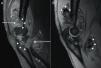

(A) Sagital T1 Fat-saturated image of the left elbow after intravenous gadolinium administration, showing an enhancing soft-tissue mass (arrows) associated to bone erosions (arrowheads). (B) Sagital T2* weighted image, showing areas of marked low signal intensity (arrowheads) suggestive of hemosiderin deposits.

A 57-year-old man with longstanding ankylosing spondylitis (AS) was treated successfully with etanercept since January 2006, except for persistent left elbow swelling. Three local corticosteroid injections and radiosynovectomy with 3mCi 186-Rhenium proved to be useless. Elbow involvement is sporadically seen in AS,1 and the persistence despite the intra-articular treatment made us consider the possibility of a coexistent arthropathy, such as an opportunistic infections (mycobacteria, fungi), synovial sarcoma, joint metastasis or lipoma arborescens. A first magnetic resonance imaging (MRI) was ordered, showing an unspecific synovial hypertrophy. Joint aspiration revealed an inflammatory non-hemorrhagic fluid with repeatedly negative cultures, and an open biopsy resulted in non-specific synovitis, ruling out infections and malignancies. In June 2010, an X-ray highlighted the development of bone erosions. A new MRI (Fig. 1) demonstrated at this time an enhancing soft-tissue mass with magnetic susceptibility effect of hemosiderin on T2*-weighted imaging, associated with subchondral bone cysts and extrinsic erosions. Surgical synovectomy was requested, and histopathologic examination noted villonodular hyperplasia and multiple multinucleated macrophages laden with hemosiderin, characteristic features of pigmented villonodular synovitis (PVNS).